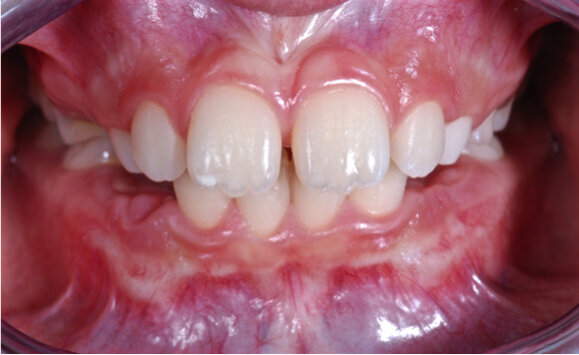

Caso 1 Paziente di anni 9,5, II Classe scheletrica, retrusione mandibolare, contrazione dell’arcata superiore, Overjet elevato (9,5 mm), compressione delle vertebre cervicali. La paziente riferisce di soffrire di cefalee continue. Dall’esame della panoramica e della teleradiografia evince una grande discrepanza tra il condilo dx e sx ed un evidente riduzione dello spazio intervertebrale in corrispondenza delle prime vertebre cervicali. La paziente è sottoposta a terapia elastodontica con AMCOP di seconda classe SC 3 con lo scopo di favorire l’espansione dell’arcata superiore e l’avanzamento mandibolare. A distanza di un anno evince un miglioramento dell’articolazione temporo-mandibolare di sx ed un aumento dello spazio intervertebrale legato a l’avanzamento mandibolare, è evidente inoltre il miglioramento dell’overbite ed overjet. A distanza di 2 anni si assiste ad un netto miglioramento dei condili grazie all’azione scheletrica dell’AMCOP ed a un netto vantaggio posturale con aumento dello spazio tra le vertebre cervicali. La malocclusione si può dire risolta anche se necessita una stabilizzazione del caso clinico attraverso lo stesso dispositivo (Figg. 2-14).

Fig. 2

Fig. 3

Fig. 4

Fig. 5

Fig. 6

Fig. 7

Fig. 8

Fig. 9

Fig. 10

Fig. 11

Fig. 12

Fig. 13

Fig. 14

Il caso clinico dimostra come la malocclusione scheletrica avesse delle forti ripercussioni sulla postura e come risolvendo la malocclusione scheletrica si ha anche un ottimo equilibrio posturale come evince dalle teleradiografie.